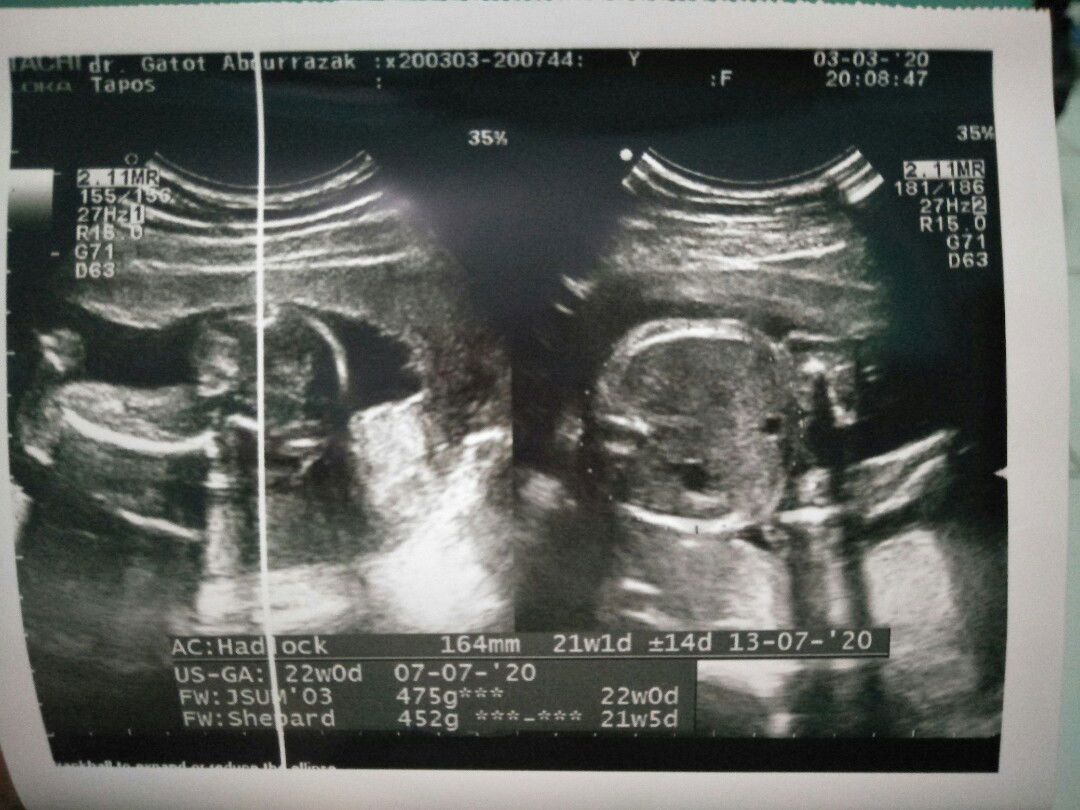

trimester ketiga

Bun kehamilanku udh 7 bulan. kenapa ya ko mual mual nih, apalagi kalo udah makan langsung muntah lagi..